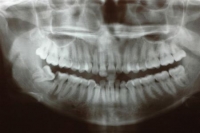

Hard and Soft Tissue Surgery Module 5 for Dental Practice

The modern day dental practitioner is expected to be capable of managing an increasing number of oral surgical problems. The commissioning of such care into the primary care sector reflects this trend. This module will cover the theory expected of a competent practitioner expected to have a good understanding of oral surgery as applied to the practice outside of specialist centres. More advanced topics will be covered but emphasis is placed upon the basic surgical skills.